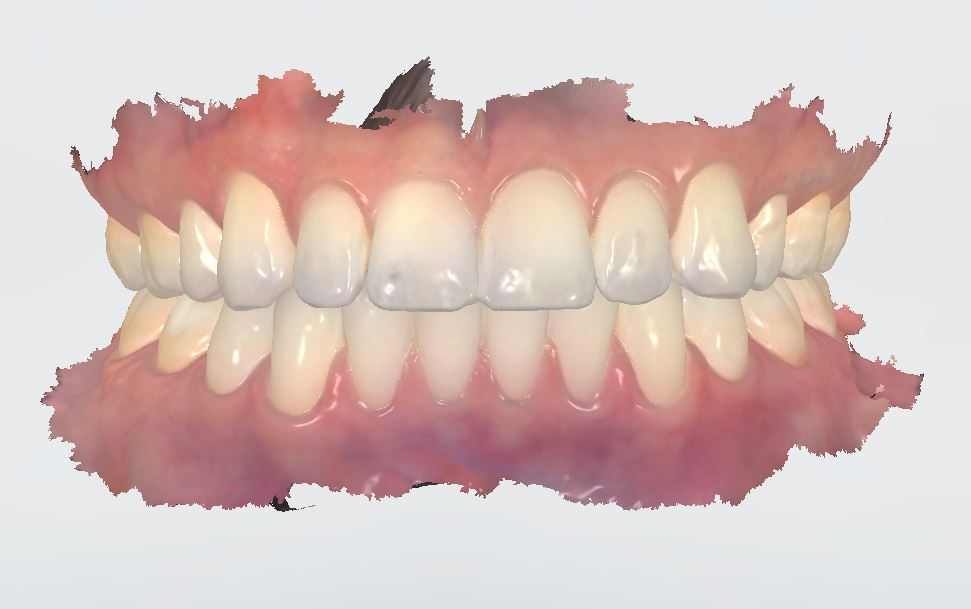

Intraoral scan or impressions.

An intraoral scan or full set of impressions must be provided.

It is critical to follow the recomended scanning protocal of aligners for your scanner. This assures accurate representations of the teeth positions - especially from side to side.